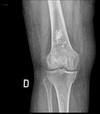

80 year old female with pain and swelling in the right knee. What is on your list of differential diagnoses in order from most to least common?

Stippled calcification = ICE 1. Chondrosarcoma 2. Enchondroma 3. Infarct